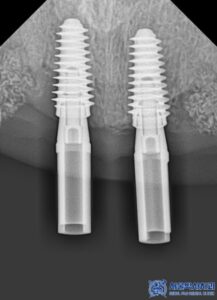

<기성 지대주와 맞춤형 지대주 비교>

✅음식물이 잘 끼지 않아 위생적

기성 지대주는 일정한 형태로 제작되어 있어

환자의 잇몸 형태와 완벽하게

맞지 않는 경우가 많습니다.

반면 맞춤형 지대주는 환자의 구강 구조에

맞게 정밀하게 제작되므로,

잇몸과의 밀착력이 뛰어나

음식물이 끼는 현상을 줄일 수 있습니다.

✅강도와 내구성이 뛰어남

맞춤형 지대주는 개개인의 구강 상태에 맞춰

설계되기 때문에 기성 제품보다 강도와

내구성이 뛰어납니다.

특히 앞니와 같은 부위는 씹는 힘보다는

심미적인 요소가 중요하기 때문에,

강도와 심미성을 모두 고려한

맞춤 제작이 필수적입니다.

✅자연스러운 심미적 효과

맞춤형 지대주는 보철물과의 연결 부위가

매끄럽게 이어져 치아가 보다

자연스럽게 보이도록 도와줍니다.

또한 잇몸 라인도 딱 맞게 제작되어

임플란트 치아가 마치 원래

내 치아처럼 보이는 효과를 줍니다.

이러한 장점들로, 서울박사치과에서는

기성 어버트먼트가 아닌

맞춤형 지대주를 사용하고 있습니다.